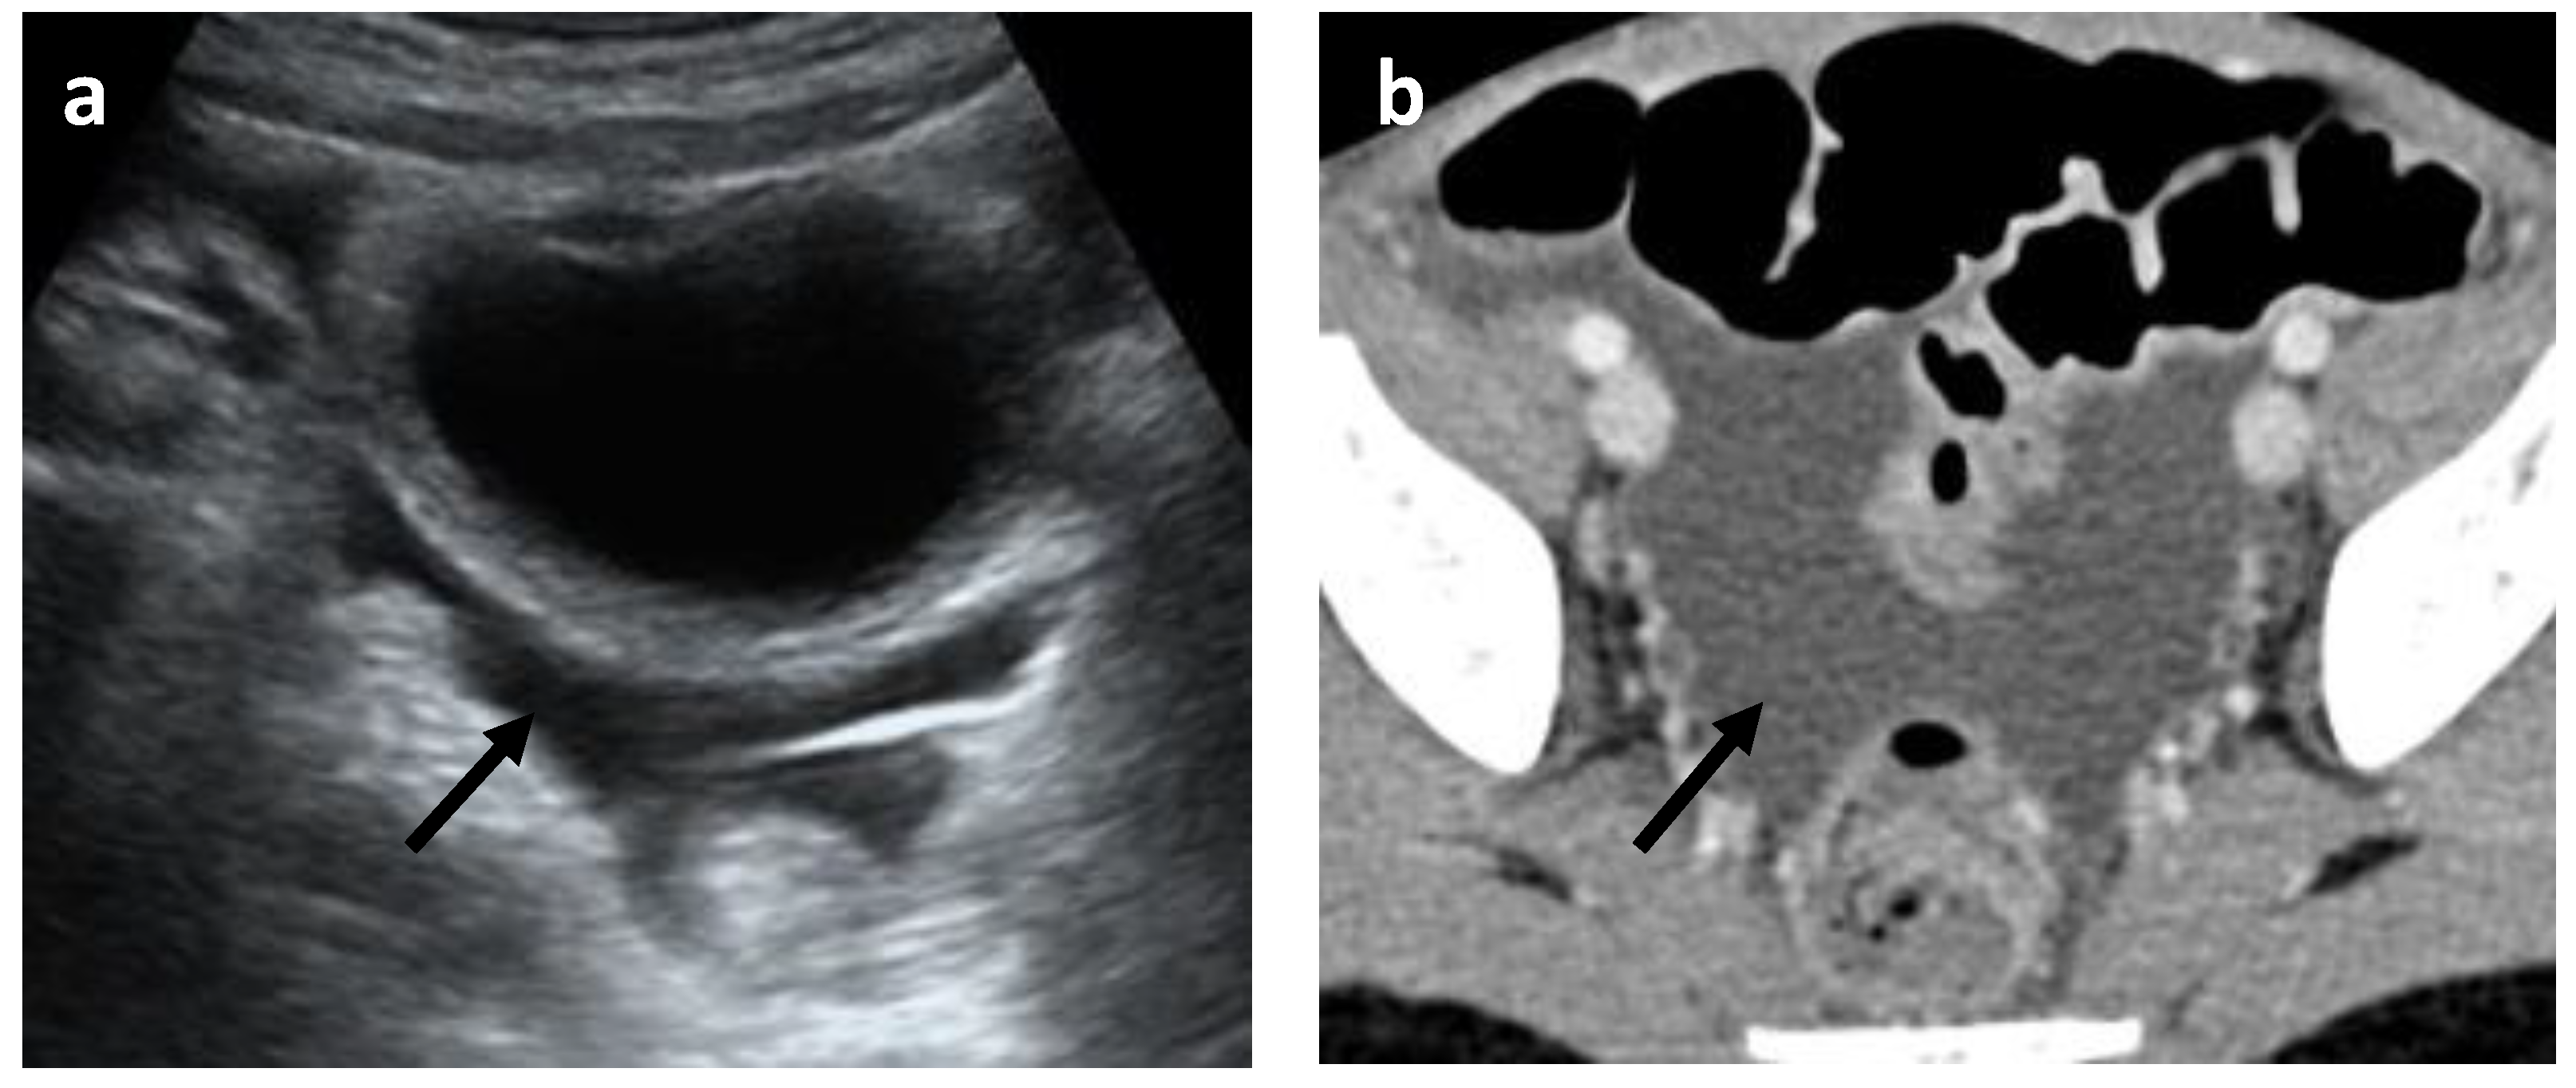

- Mesenteric and retroperitoneal lymphadenopathy (Figure 7) with mesenteric lymph nodes considered enlarged if >5 mm in short axis and retroperitoneal lymph nodes considered enlarged if >9 mm in short axis.

| Abdominal CT scan, N 20 | Mesenteric lymphadenitis | 14 | 70% | 27.5% |

| Mesenteric lymphadenitis | 28 | 54.9% | 54.9% | |

| Mesenteric lymphadenitis Diffuse | 9 | 17.6% | 17.6% | |

| Mesenteric lymphadenitis Ileocecal | 7 | 13.7% | 13.7% | |

| Mesenteric lymphadenitis Diffuse and ileocecal | 4 | 7.8% | 7.8% | |